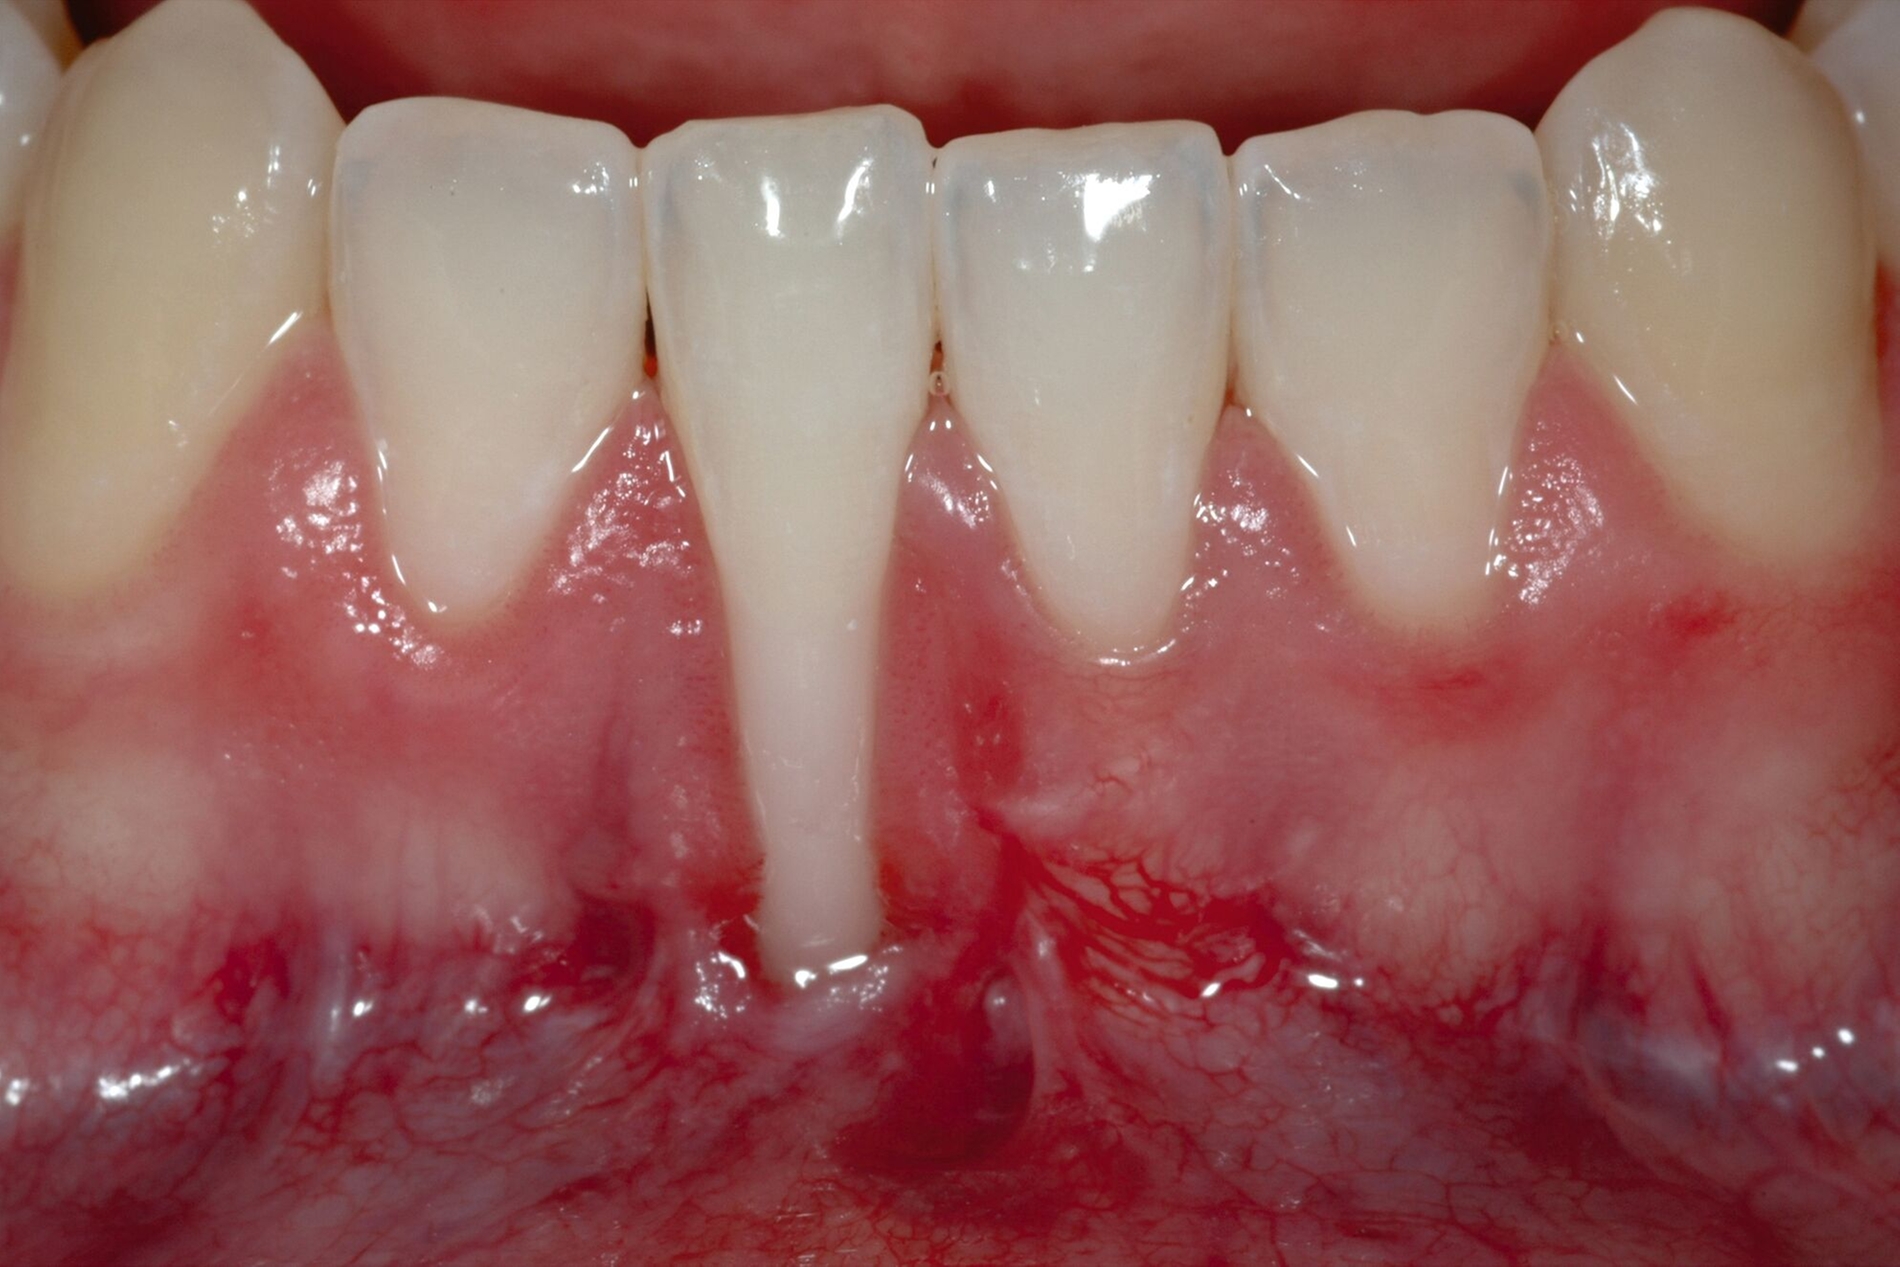

Beim lateralen Verschluss der tiefen Rezession im Rahmen der LCAT- oder LCAF-Technik ist immer mit dem Auftreten von Spannungen zu rechnen, insbesondere wenn die Rezession eine deutliche Breite aufweist. Nicht möglich ist dieses entlastungsinzisionsfreie Vorgehen, wenn mehrere tiefe Rezessionen direkt oder unmittelbar benachbart sind, da dann das Gewebe in die entgegengesetzte Richtung lateral mobilisiert werden müsste. Für diese Patienten haben Tunkel et al. eine Methode entwickelt, die grundsätzlich die Prinzipien der Koronalverschiebung nach Zucchelli, die Nelson-Technik und die LCAF-Technik verbindet und versucht, deren Vorteile zu kombinieren und deren Nachteile zu kompensieren: den „Mehrfach Gestielten Koronal Verschobenen Lappen“ (MPCAF) [Tunkel et al., 2021; Tunkel et al., 2022] (Abbildung 4). Gleichzeitig ist es damit möglich, mehrere auch direkt nebeneinander liegende Rezessionen zu decken.

Dabei wird zunächst – wie bei der LCAF-Technik – die Gingiva der tiefen Rezessionsareale exzidiert und die Inzision in gleicher Weise horizontal erweitert (Abbildung 4b). Zum Ende des gewünschten Präparationsareals wird aber eine vertikale Entlastungsinzision gezogen. Hier gibt es aber deutliche Unterschiede zur Nelson-Technik: Die Inzision liegt durch die horizontale Erweiterung weiter von der tiefsten freiliegenden Wurzeloberfläche entfernt und wird bei multiplen Rezessionen auch möglichst in den Seitenzahnbereich verlegt, damit die daraus resultierenden Narben später nicht sichtbar werden. Zudem wird die Rezession nicht gerade, sondern in einem runden Rückschnitt geführt, so dass zur Lateralisation keine Verschiebung, sondern eine Rotation durchgeführt werden kann, was trotz der seitlichen Verlagerung eine Deckung des Areals der Entlastungsinzision ermöglicht.

Jetzt wird beginnend an einer Seite der erste Lappenanteil nach dem Prinzip teilschichtig-vollschichtig-teilschichtig gelöst und im Bereich der ersten tiefen Rezession mittels feiner monofiler Nähte mit dem proximalen Lappenanteil vernäht. Dieser wird daraufhin gelöst und bei der nächsten tiefen Rezession erneut mit dem nahe gelegenen Lappenanteil verbunden. Dieser Vorgang wird fortgeführt, bis so erneut ein großer gesamter Lappen entstanden ist, der koronal verschoben werden kann (Abbildung 4c). Das weitere Vorgehen ist exakt wie bei der LCAF-Technik: Entepithelialisierung der Papillenareale, Gewinnung des Transplantats, Applikation von EDTA-Gel und Schmelz-Matrix-Proteinen, Fixation des Transplantats und Fixierung des Lappens nach koronal (Abbildungen 4d bis 4f). Die runden Entlastungsinzisionen lassen sich meist ohne größere Mühe verschließen, selbst wenn multiple tiefe Rezessionen vernäht worden sind.

Der MPCAF ist neben der von Bernimoulin beschriebenen Methode eine von nur sehr wenigen Techniken, mit der multiple tiefe RT1-Rezessionen gedeckt werden können. Allerdings kann eine vollständige Narbenfreiheit nicht gewährleistet werden. Daher ist es zu empfehlen, bei dieser Technik den Lappen mindestens bis zum Eckzahn oder ersten Prämolaren auszudehnen. Eine Überdeckung von mehr als 2 mm der Schmelz-Zement-Grenze ist möglich, so dass eine hundertprozentige Deckung erreichbar ist. Allerdings ist aufgrund der Verschiebung und des Vernähens mehrerer kleiner Lappenanteile die Methode äußerst techniksensibel und daher nur erfahrenen Anwendern zu empfehlen.